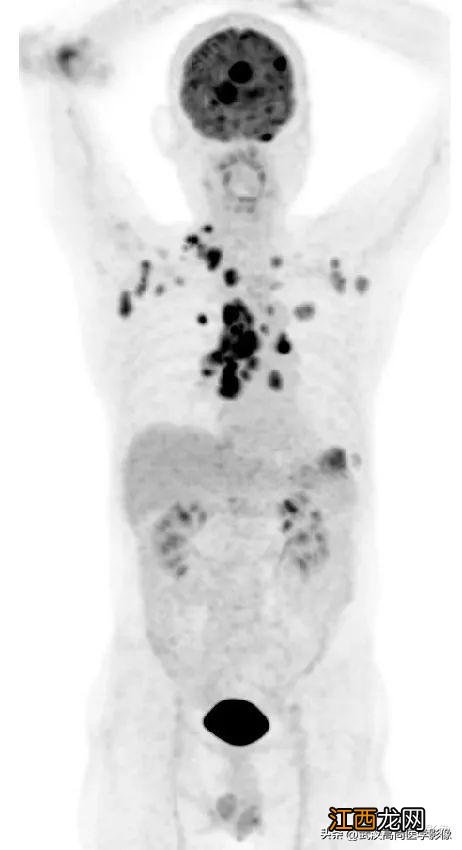

本次主要分享一些PET/CT工作中的测量仪常见病例 , 观察分析肺实性结节的破坏力 。

PET/CT表现:

全身(右侧颈部、双侧锁骨2mm上区、双侧腋窝、右侧胸小肌后间隙、右侧肺门、纵隔、胰腺周围)多发淋巴结肿大 , 最大约3.8cm×3.3cm , FDG高摄取 , SUVmax6.6 。

脾脏真实一低密度结节 , FDG高摄取 , 2cm2疤痕是几厘米 , SUVmax为3.6 。

左侧第2、7肋骨质真实破坏 , 合并测量标准病理性8cm骨折 。

右肺上叶后段一实性结节 , 大小约1.4cm×1.0cm×1.2cm , 边缘分叶征、棘状突起 , 邻近胸膜稍牵拉 , FDG高摄取 , SUVmax6.6 。

右肺上叶后段周围型肺癌 , 伴淋巴结、脑、脾脏、肋骨多发转移 。